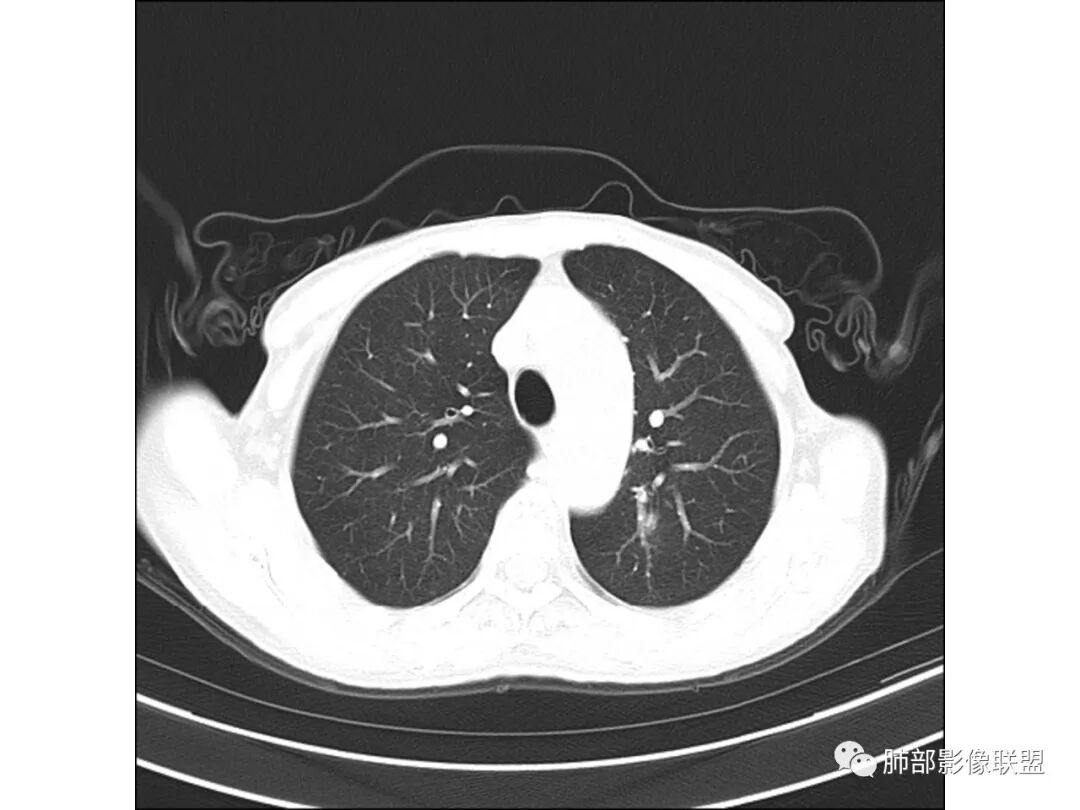

慢性迁延不愈患者 发热伴脓痰 双肺多发小结节伴磨玻璃影 左肺下叶体积缩小 支气管扩张伴实变 实变内支气管不规则 平扫密度尚均较肌肉稍低 支气管扩张感染基础上合并淋巴瘤待查 建议增强穿刺

老年女性,慢性病程,有反复咯血、发热,左下胸廓塌陷,双肺下叶多发片状实变影,伴多发结节,左下肺实变为主伴卫星灶,支气管扩张,伴虫噬样空洞及支气管壁钙化,首先考虑结核,鉴别粘液腺癌

老年丶反复发作2年,但双肺下叶多发腺泡结节,延气道分布,影像不符合陈旧病变,左下实变影,伴牵拉支扩,考虑慢性病变首先考虑吸入性肺炎,建议结合病史是否有隐性误吸,可查胃镜、气管镜丶钡透,除外食管、气管瘘。鉴别腺癌丶放线菌丶努卡菌丶NTM

患者老年女性,反复咳嗽 咳痰 活动后胸闷 气短,胸ct:病变以左肺下叶体积缩小,呈大片实变,实变组织内可见 左肺下叶支气管开口扩张,右肺下叶背段多发结节样病灶,周围有毛玻璃影。良性考虑感染性病变,ABPA ?结核?;恶性考虑:粘膜相关淋巴瘤。

双肺多叶段多发腺泡结节,延气道分布,双下肺为诸,左下肺大片实变影,伴牵拉支扩,老年人首先考虑支气管肺炎。鉴别腺癌。

双下肺多发腺泡结节,左肺下叶实变,彭隆,结核伴感染,鉴别结核伴粘液腺癌。

双肺下叶多发片,结节,左下肺实变,局部膨隆,粘液腺癌?鉴别结核。

晨读病例,老年女性,病程长,左侧胸廓缩小,双下肺叶多发片状实变影,伴多发结节及树芽征,左下肺实变,有坏死空洞,支气管扩张壁增厚有钙化,考虑结核,鉴别粘液腺癌,淋巴瘤,排除异物

1.双肺斑片影、大小不等结节影,边界不清,密度较均一,钙化不多见,可见树丫。